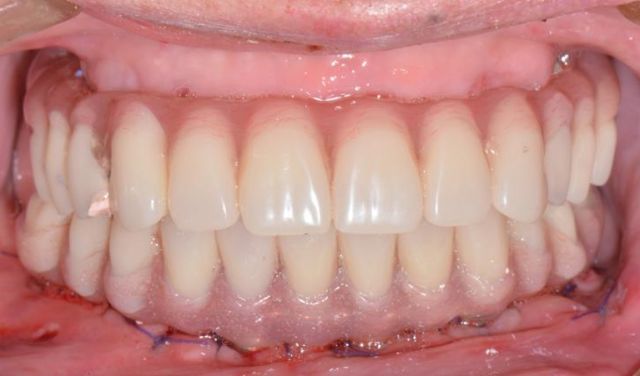

精彩案例: